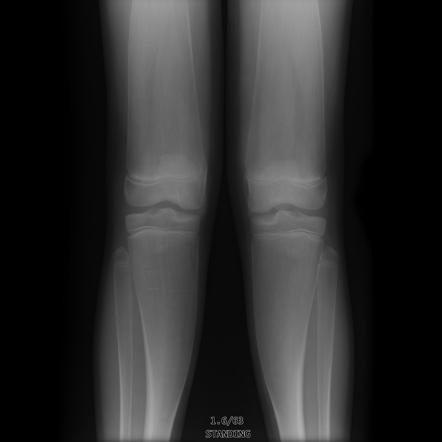

Expansile lytic bone lesion, B9